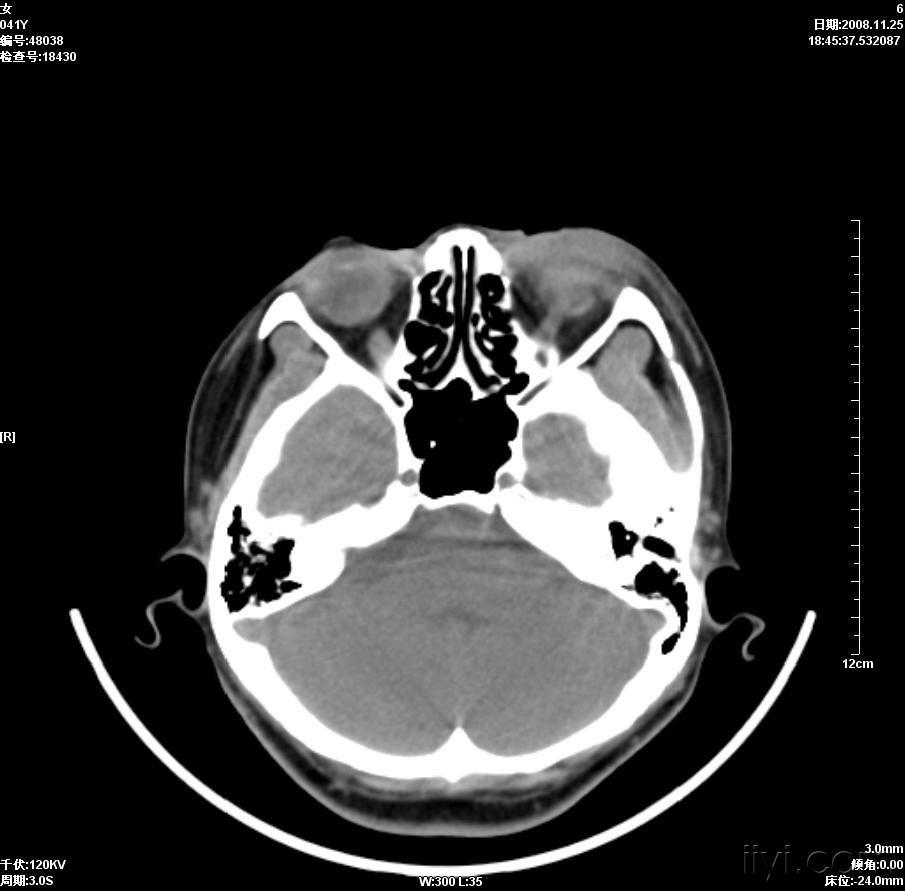

晶状体移位ct病例